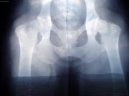

Obr.2: Artrotické změny na kyčelních kloubech 6 letého německého ovčáka s dysplazií. Tyto změny se vyvíjí postupně a až ve vyšším věku pacienta.

Dysplazie kyčelního kloubu je velmi častou vrozenou vadou u velkých a středních plemen. U většiny z nich se provádí povinné RTG vyšetření před uvedením do chovu.